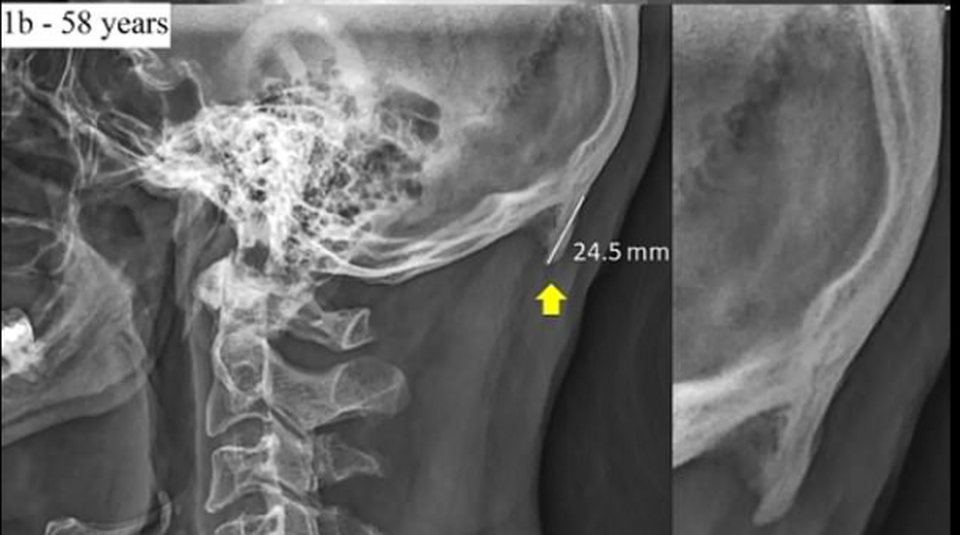

Một trường hợp khác của bệnh nhân đã 58 tuổi với phần xương lồi ra ngắn hơn so với người 28 tuổi.

Theo các nhà nghiên cứu, "cái đuôi" sinh ra bởi cách chúng ta nhìn xuống điện thoại và màn hình máy tính xách tay mỗi ngày. "Sự thay đổi cấu trúc não bộ có thể hình thành do sự căng thẳng, ức chế, khiến một vài bộ phận của cơ thể mà chúng ta thường sử dụng đã phát sinh thêm", tiến sĩ Shahar cho biết sau khi chụp X-quang hơn 1.000 hộp sọ của những người trong độ tuổi từ 18 đến 86.

Cũng theo nghiên cứu, hiện tượng này bắt gặp phổ biến nhất ở những người từ 18 đến 30 tuổi. Tuy nhiên, cũng không loại trừ khả năng xuất hiện cả ở những trường hợp nhỏ tuổi hơn, khi cấu trúc xương còn chưa được định hình rõ ràng, nếu như thường xuyên có những tư thế ngồi sai.

Tiến sĩ Shahar cho biết mặc dù các khối xương có thể sẽ không gây ra bất kỳ tác động gây hại nào, nhưng chúng có thể không bao giờ biến mất. Vì vậy bạn có thể bị mắc kẹt với chúng "mãi mãi".